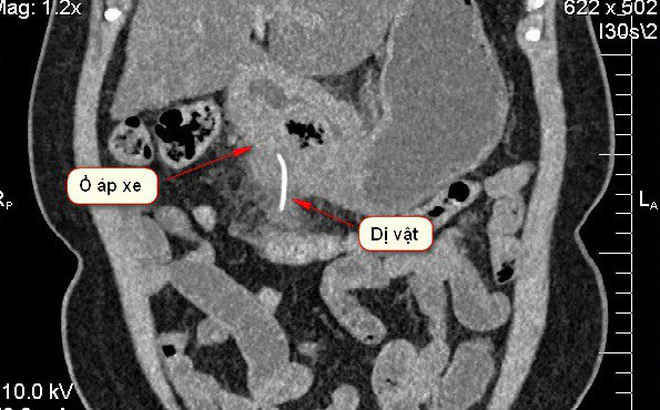

Ảnh chụp X-quang dị vật nằm trong dạ dày bệnh nhân. Ảnh:BVCC.

Sau khi thực hiện các kỹ thuật cận lâm sàng và chụp hình ảnh cắt lớp vi tính CT- Scanner bác sĩ phát hiện một tổn thương khu trú, có dị vật cản quang trong thành dạ dày vùng môn vị. Ê-kíp nghi ngờ dị vật có thể bằng kim loại, có dấu hiệu nghi áp xe thành dạ dày vùng hang môn vị.

Sau khi mở bụng, tiến hành thám sát nhận thấy mặt sau hang vị dày dính vào mạc treo đại tràng ngang. Kíp mổ phát hiện ở đại tràng ngang có xương cá dài 5cm, tiến hành lấy dị vật ra khỏi cơ thể bệnh nhân. Sau đó, bác sĩ tiến hành khoét bỏ ổ loét viêm đường kính 3 cm, gửi giải phẫu bệnh lý, khâu lại dạ dày.